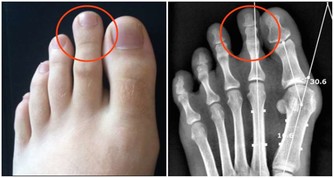

事實上,絕大部分的近視都是因為眼軸拉長所導致,遠方的光線經過眼角膜及晶狀體折射後,只聚焦在視網膜的前面,導致所看的物體影像模糊不清楚,要靠近物體,讓光線可以聚焦在視網膜上才看得清楚,這就是近視。絕大部分的近視都是因為眼軸拉長所致,只有相當少部分的人是因為角膜與晶狀體不協調。

兒童一旦近視,度數就會持續增加,近視的眼軸像吹氣球般越吹越長,到成年才會停止。眼軸越拉長,眼睛的組織就會越薄越脆弱,容易產生很多近視並發症。